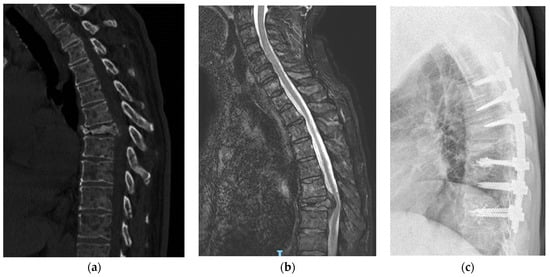

2.3. Surgical Technique